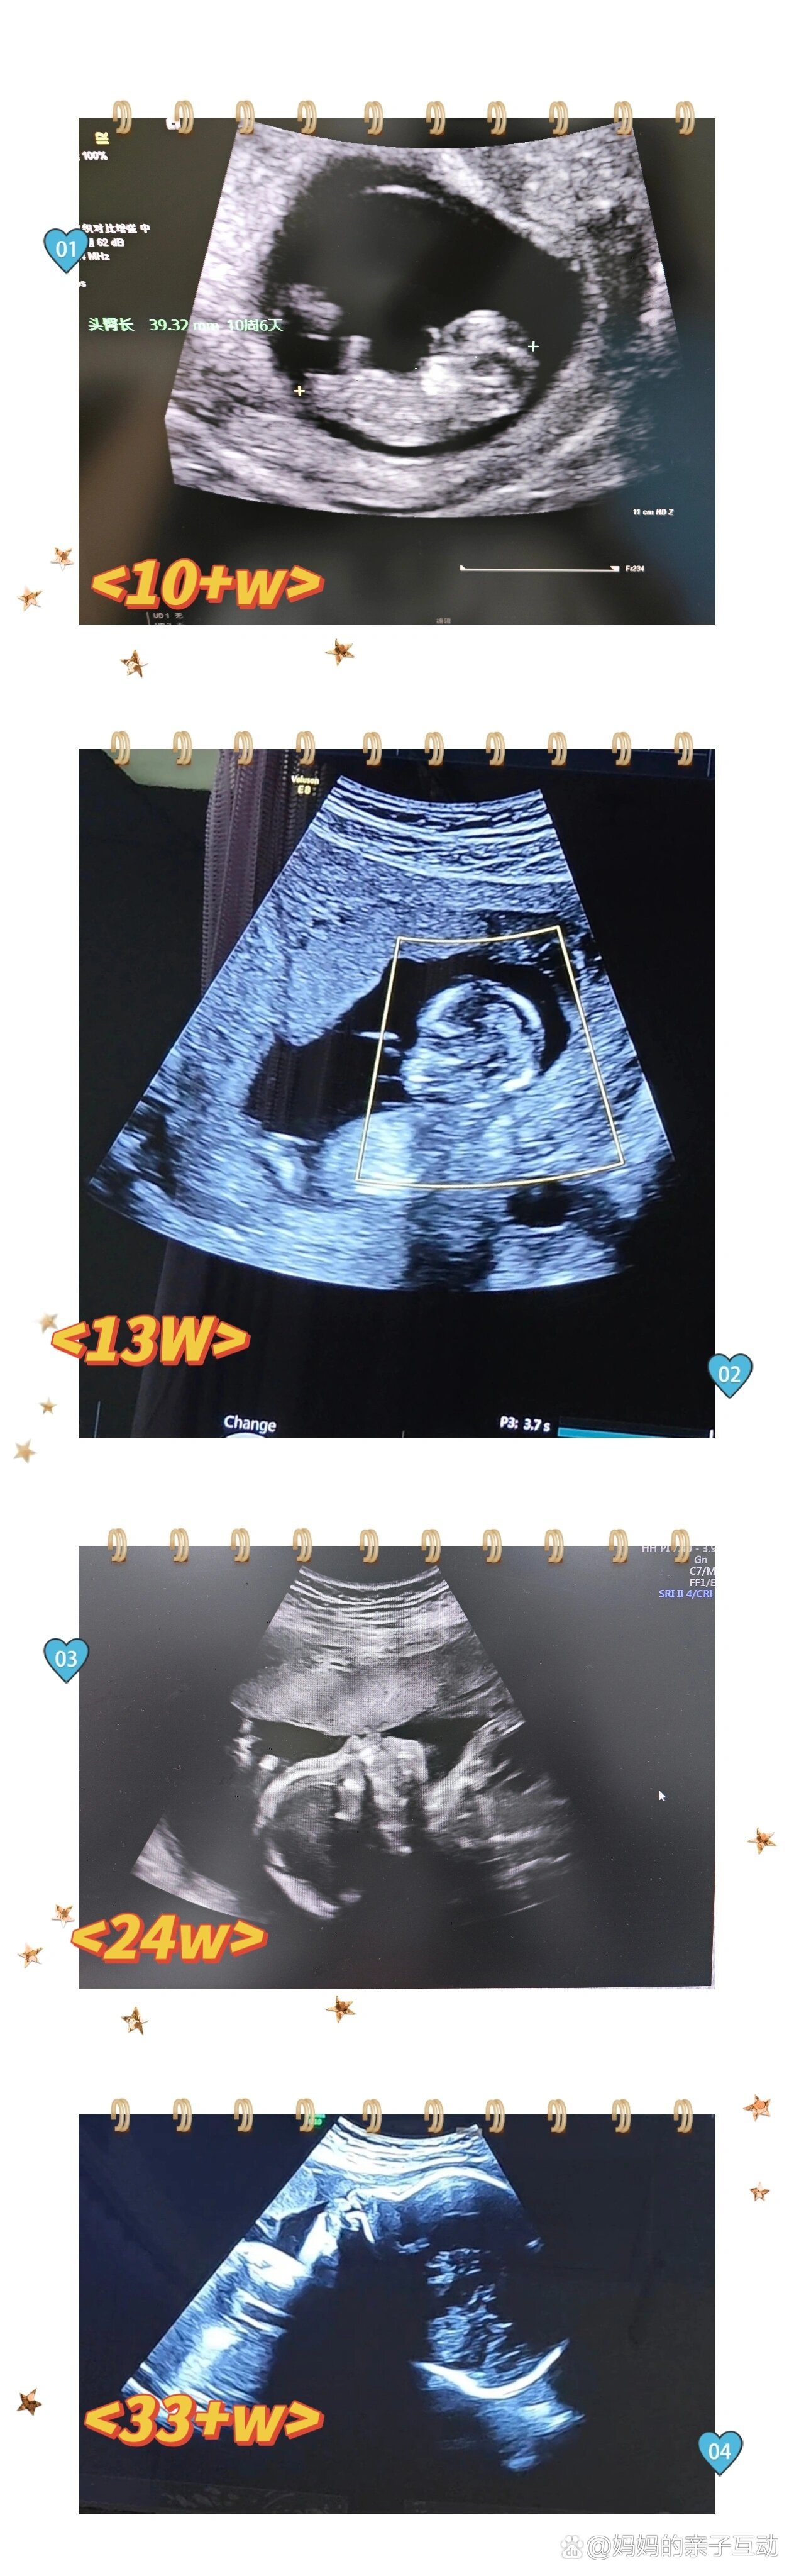

宝宝超声照